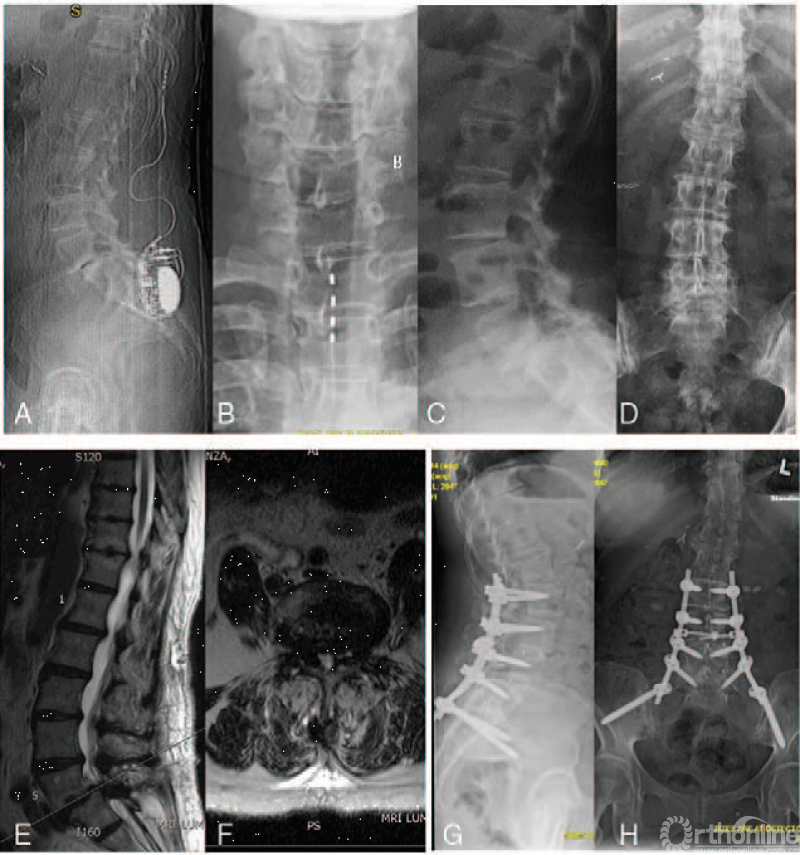

65岁女性,椎板切除术后L5/S1椎体滑脱用脊髓电刺激器治疗失败(A和B),移除SCS(C和D)及滑脱复位固定,症状缓解